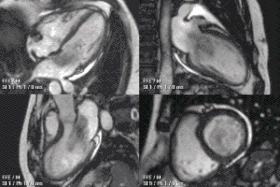

Children and congenital heart disease

Congenital heart defects are the most common type of major birth defect. Accurate diagnosis is essential for the development of appropriate treatment plans. CMR can provide comprehensive information about the nature of congenital hearts defects in a safe fashion without using x-rays or entering the body. It is rarely used as the first or sole diagnostic test for congenital heart disease.

Rather, it is typically used in concert with other diagnostic techniques. In general, the clinical reasons for a CMR examination fall into one or more of the following categories: (1) when echocardiography (cardiac ultrasound) cannot provide sufficient diagnostic information, (2) as an alternative to diagnostic cardiac catheterization which involve risks including x-ray radiation exposure, (3) to obtain diagnostic information for which CMR offers unique advantages such as blood flow measurement or identification of cardiac masses, and (4) when clinical assessment and other diagnostic tests are inconsistent. Examples of conditions in which CMR is often used include tetralogy of Fallot, transposition of the great arteries, coarctation of the aorta, single ventricle heart disease, abnormalities of the pulmonary veins, atrial septal defect, connective tissue diseases such as Marfan syndrome, vascular rings, abnormal origins of the coronary arteries, and cardiac tumors.